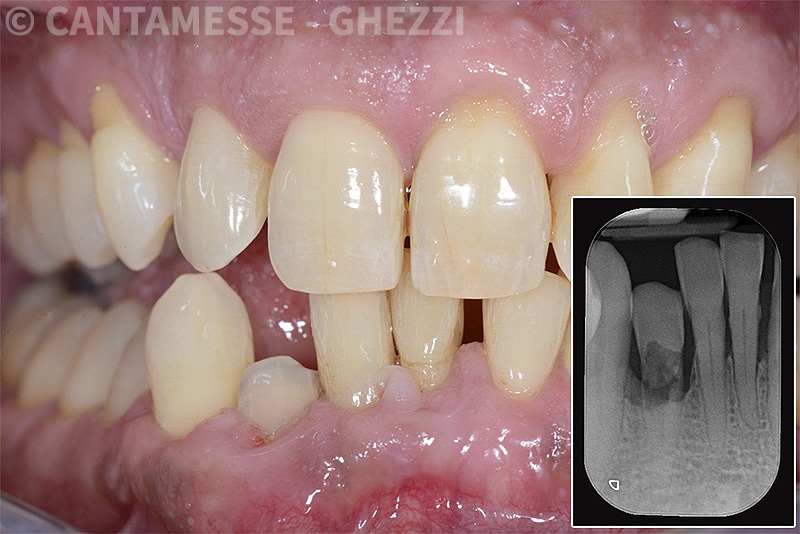

PREMESSA: in seguito all’estrazione dell’incisivo laterale superiore di destra, resasi necessaria per cause batteriche, si decide di affrontare il caso con il posizionamento di un impianto in sostituzione dell’elemento mancante dopo guarigione del sito infetto. Con tecniche rigenerative sia dei tessuti ossei mancanti a causa dell’infezione pregressa, sia dei tessuti gengivali che appaiono inizialmente troppo spostati in alto, si ripristina una corretta morfologia delle parabole (contorni) gengivali e delle papille interdentali (triangoli di gengiva tra due denti vicini).

Vengono utilizzati 2 tipi di provvisori: il primo, cementato ai denti vicini, viene utilizzato dal momento dell’estrazione del dente fino ad impianto osteointegrato (circa 6 mesi); il secondo, avvitato direttamente all’impianto, ha una funzione di prova estetica ma soprattutto di guida per la maturazione dei tessuti gengivali peri-implantari portandoli verso la maturazione completa prima di posizionare la corona finale in disilicato di litio.